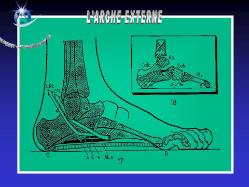

Anatomie du pied

Le squelette du pied est composé de 28 os qui se combinent en de nombreuses articulations.